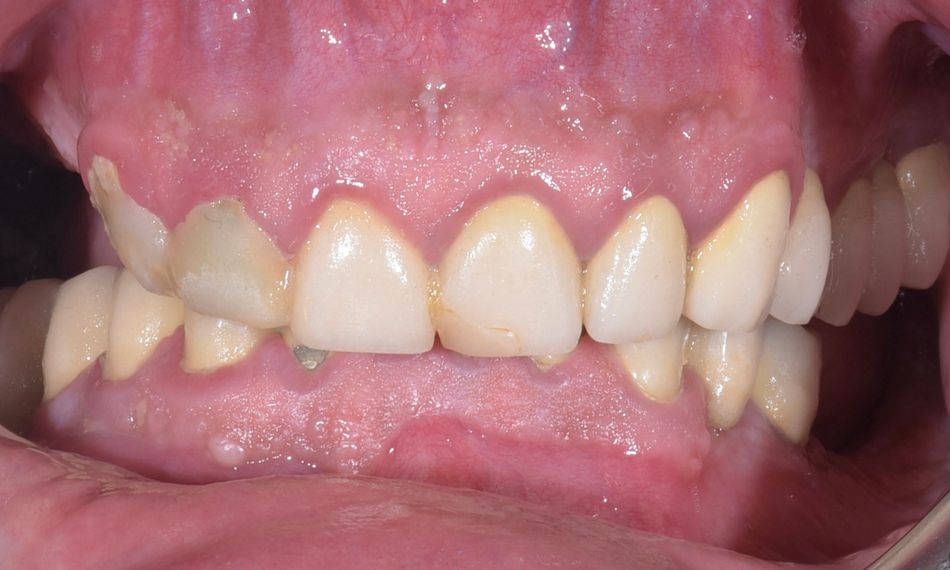

In the extraoral assessment, the patient exhibited a slightly concave lower profile. Upon smiling, the absence of posterior teeth was evident, with the upper teeth showing a slight palatal inclination contrary to the patient’s esthetic preferences (Figs. 1-3).

The intraoral assessment exposed a deep bite, accompanied by a hopeless dentition with multiple decay and root fractures following the failure of full-arch teeth-supported ceramic prostheses in both the mandible and maxilla (Fig. 4). Subsequent examination of the periodontal status indicated inadequate plaque control, along with widespread gingival inflammation and bleeding upon probing (BoP). Deep probing pockets further accentuated the challenging periodontal condition.